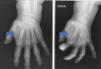

Mujer de 78 años, que consulta por tumoración en cara anterior de la mano izquierda a nivel del primer dedo de 3 meses de evolución con aumento del tamaño progresivo. En la exploración física se palpa tumoración blanda e indolora de más de 1cm.

Se solicitaron radiografías simples (fig. 1), ecografía (fig. 2) y resonancia magnética (fig. 3).